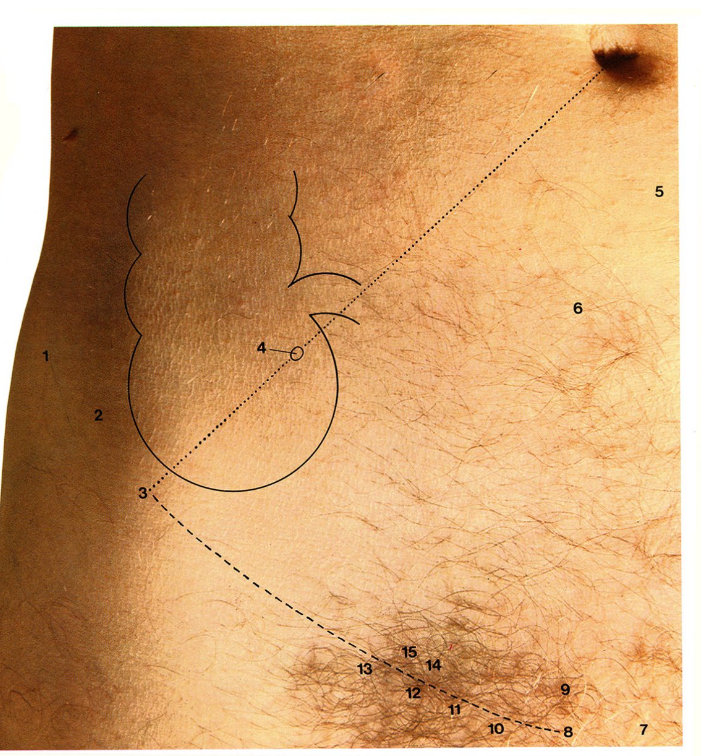

Les positions principales de l'appendice rencontrées en chirurgie ou en post mortem:

rétrocæcale

pré-iléale

post-iléale

sous-cæcale

pelvienne

palpation appendice

« point de McBurney »

zone de la paroi abdominale inférieure droite → position variable affectée par la posture et distension